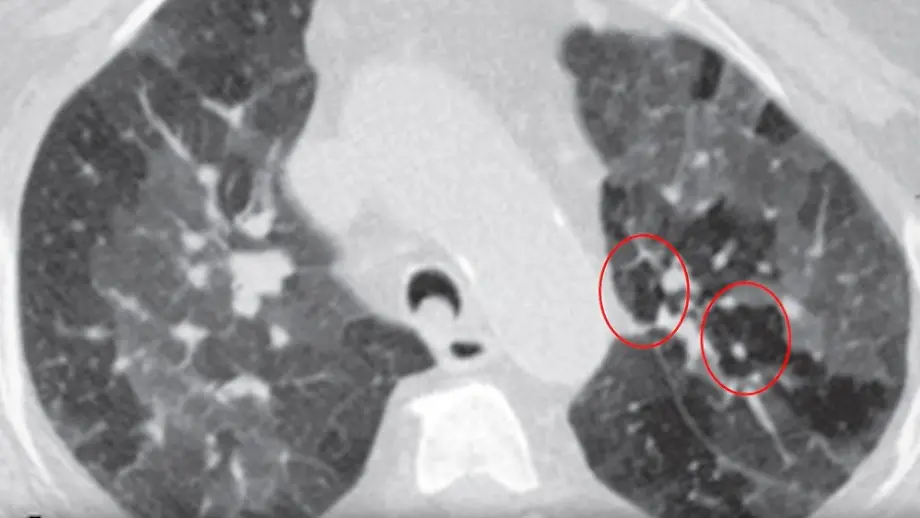

"Geht keine Luft mehr rein und raus"Vapen kann zu gefährlicher "Popcornlunge" führen

16.08.2025, 15:02 UhrVapen hat sich bei vielen, gerade jungen, Erwachsenen als beliebte Alternative zu klassischen Zigaretten etabliert. Doch der Inhaltsstoff Diacetyl kann eine sogenannte "Popcornlunge" verursachen. Lungenarzt Dr. Matthias Krüll erklärt das gefährliche Phänomen.